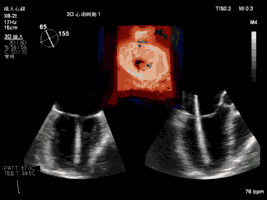

本例手術(shù)使用TrueVue實(shí)時(shí)三維雙容積視野同時(shí)顯示二尖瓣左房觀和左室觀,畫(huà)面清晰,界面友好,使得手術(shù)操作“如虎添翼”,更加便捷和安全。本例手術(shù)導(dǎo)管操作總時(shí)間(從穿刺心尖到閉合心尖)僅為10分鐘。系列圖像如下:

夾合術(shù)中:三維心超示輸送鞘跨瓣